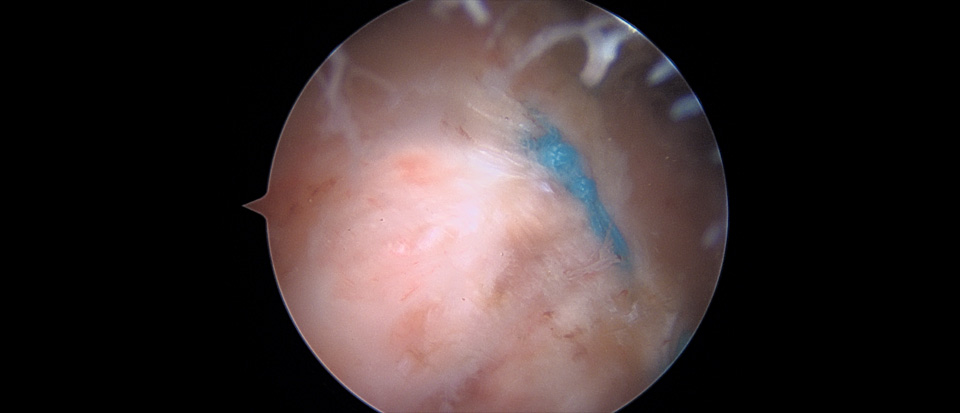

수술중 관절경으로 파열이 확인된다.

- 환자 동의하에 게시된 이미지입니다.

관절경을 이용해서 파열된 회전근개를 봉합한다.